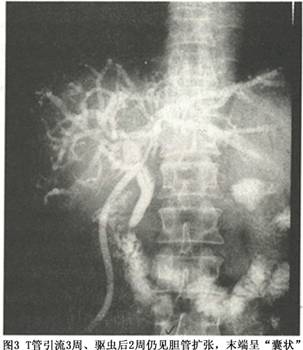

(2)手术治疗:针对华支睾吸虫引起的原发、继发胆道结石、梗阻,有相当一部分病人需手术治疗,治疗原则是:通畅引流、解除狭窄、继发病治疗、服药排虫。常采用的术式是胆囊切除、胆总管探查、胆肠吻合术。不论采用何种术式,在胆管内置T管、支架管或U型管,术后不仅可以观察胆汁引流情况,而且可观察驱虫效果,决定是否需要反复排虫治疗。外科手术不能替代药物治疗,在术后患者一般情况好转后,大约术后1周左右开始口服驱虫药,常可见大量吸虫由引流管排出,待吸虫接近排净后再拔T管或支架管。值得注意的是,治疗后的肝内胆管扩张不会在短时间内恢复正常(图3),与胆管腺瘤样增生、胆管壁变硬、纤维化有关,这些改变不容易因驱虫治疗而逆转,而且虫尸的毒素仍在一段时间内存在,胆管仍对致癌物质敏感,应经常随诊。

2.胆道造影 经皮肝穿刺胆道造影(PTC),经十二指肠镜逆行胰胆管造影 (ERCP),以ERCP较常用。胆道造影的特点是:扩张的胆管不是以“树枝状”由粗变细,而是因虫体阻塞,增宽的胆管分枝突然截断,呈“秃枝状”(图1)或末端呈“囊状”,扩张的胆管内也可见细丝状或椭圆形透亮区。 医学百科网 | YxBaike.Com